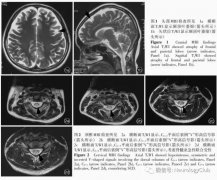

[其他中毒] 临床案例:滥用笑气中毒致神经系统损害一例(一氧化二氮,N2O) 日期:2018-03-21 11:44:36 点击:2966 好评:0

患者女性,20岁,主因四肢麻木、无力并进行 性加重2周,排尿困难4d,于2015年10月30日收入中日友好医院。患者于2周前在美国上学途中无明显诱因突然出现黑蒙、意识丧失伴跌倒,数分钟后自行...